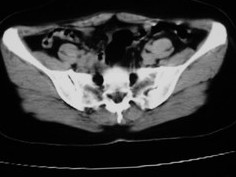

女42岁肛门下坠感4月余.

子宫轻度右倾,体后方见小似新月形低密度区,边界清楚。余所见无明显异常。

考虑:子宫直肠窝少量积液(盆腔炎所致)。

子宫轻度右倾,体后方见小似新月形低密度区,道格拉斯窝周围间隙欠清晰,有索条模糊影阴,多考虑:肛周脓肿可能性大。

子宫轻度右倾,体后方见小似新月形低密度区,道格拉斯窝周围间隙欠清晰,有索条模糊影阴,多考虑:肛周慢性感染可能。